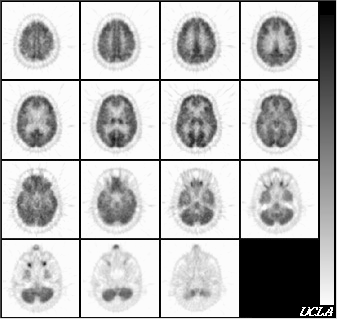

(C) 1994 Crump Institute for Biological Imaging

UCLA School of Medicine